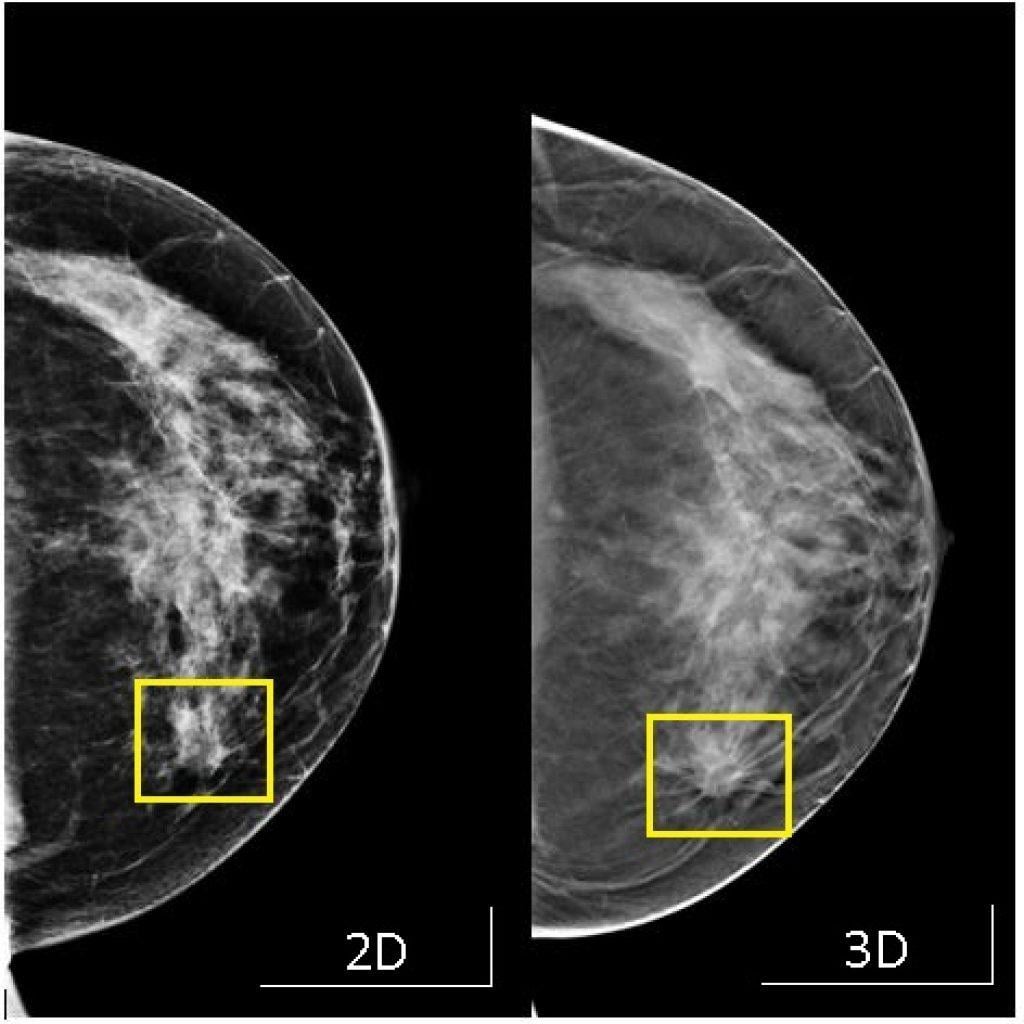

乳癌是最常見的女性癌症,本港每14名女士便有一人最終會患上乳癌。乳房造影檢查是及早發現乳癌的有效方法,美國一項有逾百萬女性參與的大型研究發現,3D立體乳房造影檢測乳癌的準確率比傳統2D造影高逾兩成,尤其有助偵測乳房組織密度較高女士的異常情況。

數據分析顯示,每進行1,000次3D造影就發現5.3宗乳癌,而2D則找到4.5宗個案。而3D造影的假陽性及假陰性的機會都較低。

3D乳房造影表現比2D的好。

資料顯示,沿用多年的2D乳房造影,從乳房正面和側面拍攝再組合成一個影像,以致部分區域可能會出現重疊,而檢測乳房的準確率約為87%。至於3D乳房造成則從不同角度拍攝影像,呈現每一層乳房組織的狀態,再利用電腦製成立影像。